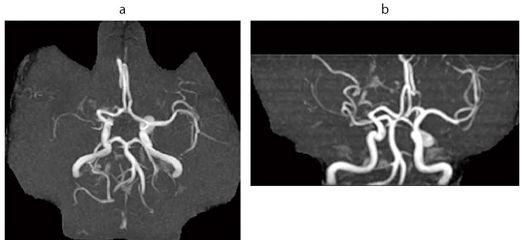

図2 脳動脈瘤(右内頸動脈瘤) 64歳,女性。クモ膜下出血の家族歴がある。本人,ご家族が根治術を希望され,紹介となった。MRA,3D TOF,VR像(脳ドック症例)

図2 脳動脈瘤(右内頸動脈瘤)

64歳,女性。クモ膜下出血の家族歴がある。

本人,ご家族が根治術を希望され,紹介となった。

MRA,3D TOF,VR像(脳ドック症例)